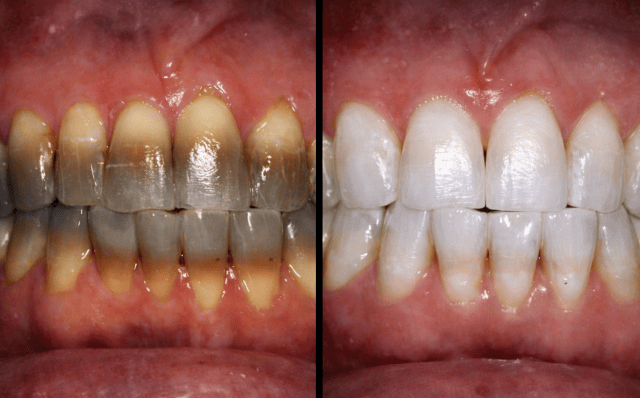

How much can teeth improve with tetracyclines?

Results vary depending on each patient, but in many cases it is possible to achieve very significant improvements in tooth colour, even in cases of deep staining. Teeth whitening can change the colour of teeth affected by tetracycline, lightening and evening out the colour of the enamel to improve dental aesthetics.

Stains caused by tetracyclines can appear in different colours, such as yellow, brown or grey, which significantly affects the appearance of the smile. The treatment aims to improve the appearance of the teeth by restoring a more uniform and natural colour.

Although in some very severe cases it may be necessary to combine whitening with other cosmetic treatments, teeth whitening is usually the first option because it is conservative and minimally invasive.